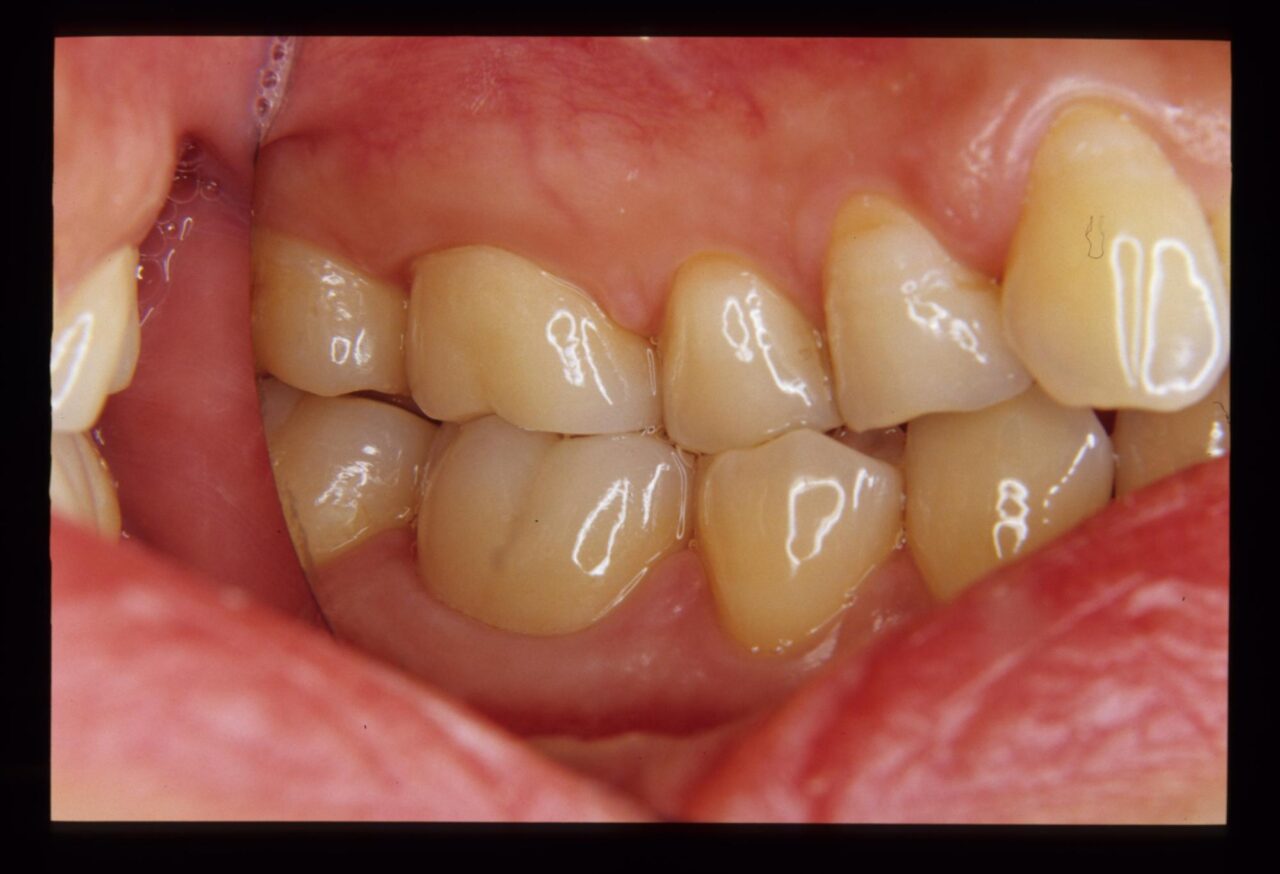

根管充填後、ファイバーコアにて築造して最終的な修復部を装着しました。2005年より経過が良好で現在に至ります。